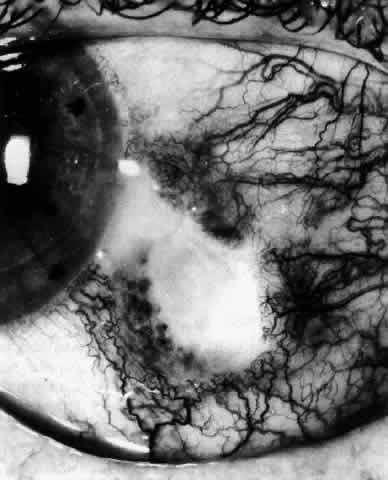

In contrast to simple episcleritis, the infiltration and edema of nodular episcleritis are localized to one part of the globe, forming a nodule and some surrounding congestion (Color Plate 1B). The nodule can be moved over the underlying sclera, which is not edematous. The scleral plexus of vessels can be distinguished deep to the nodule, lying flat on the sclera and slightly congested but otherwise normal in color and configuration (Figs. 15 and 16). Episcleral nodules may be single or multiple but do not undergo necrosis (see Fig. 16). After multiple attacks of nodular episcleritis in the same location, the superficial lamellae of the sclera show some alteration and become slightly more transparent in this one area.

Fig. 15. Episcleritis. In episcleritis, the vascular networks of the conjunctiva, episclera, and sclera are all congested. The edema is confined to the episcleral tissue so that the reflected light from the sclera shows no displacement. (Watson PG, Hayreh S, Awdry P: Episcleritis and scleritis. Br J Ophthalmol 52(3):278–279, 1968)

Fig. 16. Deep vessels, which are normal in configuration, can be traced beneath edematous nodules lying flat on the sclera. (Watson PG: Connective tissue disorders and the eye. In: Recent Advances in Ophthalmology, Vol 5, pp 214–277. London, Churchill-Livingstone, 1975)